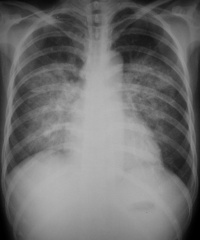

肺水肿间质期的X线表现主要为肺血管纹理模糊,增多,肺门阴影不清,肺透光度降低,肺小叶间隔增宽。两下肺肋膈角区可见与胸膜垂直横向走行的KerleyB线,偶见上肺呈弧形斜向肺门较KerleyB线长的KerleyA线。肺泡水肿主要表现为腺泡状致密阴影,呈不规则相互融合的模糊阴影,弥漫分布或局限于一侧或一叶,或从肺门两侧向外扩展逐渐变淡成典型的蝴蝶状阴影。有时可伴少量胸腔积液。但肺含量增加30%以上才可出现上述表现。CT和核磁共振成像术可定量甚至区分肺充血和肺间质水肿,但费用昂贵。

• 分布和形态呈多样性,可呈中央型、弥漫型和局限型。中央型表现为两肺中内带对称分布的大片状阴影,肺门区密度较高,形如蝶翼称为蝶翼征。局限型可见于一侧或一叶,多见于右侧。除片状阴影外,还可呈一个或数个较大的圆形阴影,轮廓清楚酷似肿瘤